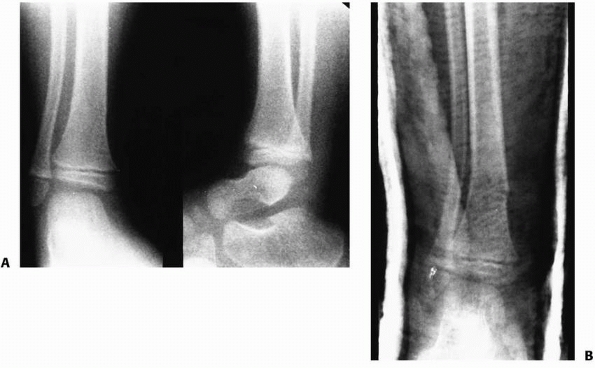

|

FIGURE 25-27 A. Anteroposterior and lateral radiographs of a grade IIIB open fracture of the distal tibia and fibula. B.

Anteroposterior and lateral radiographs after fracture reduction and stabilization with an Ilizarov circular fixation frame. (From Sharps CH, Cardea JA. Fractures in the shaft of the tibia and fibula. In: MacEwen GD, Kasser J, Heinrich SD, eds. Pediatric Fractures: A Practical Approach to Assessment and Treatment. Baltimore: Williams & Wilkins, 1993:325, with permission.) |